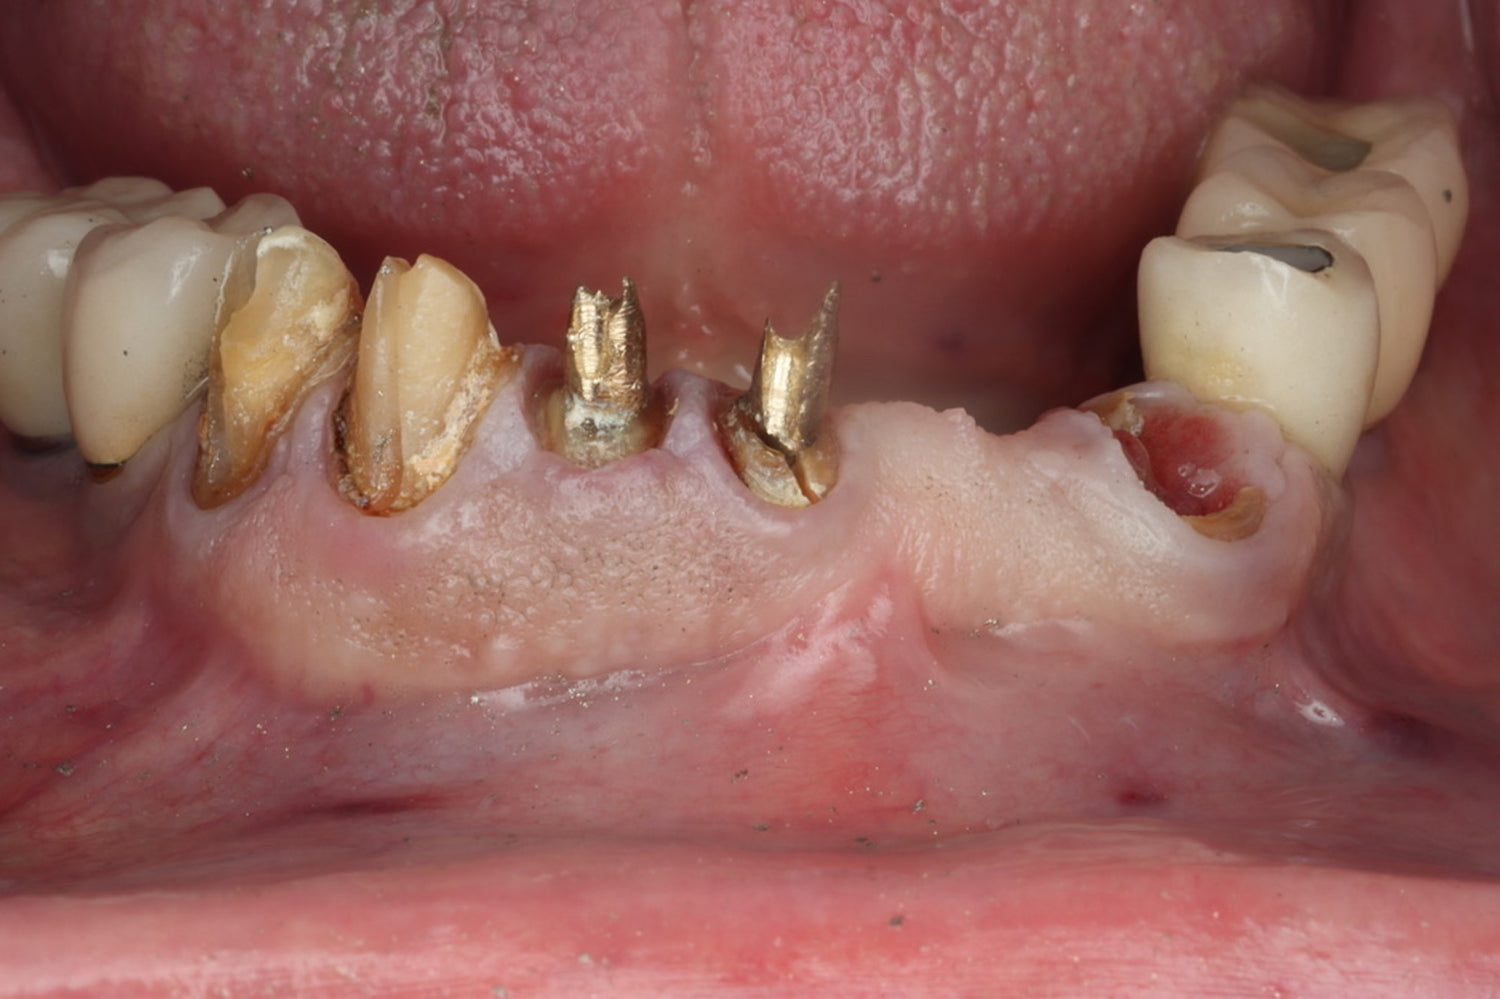

- Explore the science behind Partial Extraction Therapy and understand its emergence as the gold standard in modern implantology

- Master Partial Extraction Therapy through systematic, step-by-step instruction and hands-on practice

Partial Extraction Therapy hands-on techniques:

- Socket shield,

- Root submergence,

- Socket shield modifications